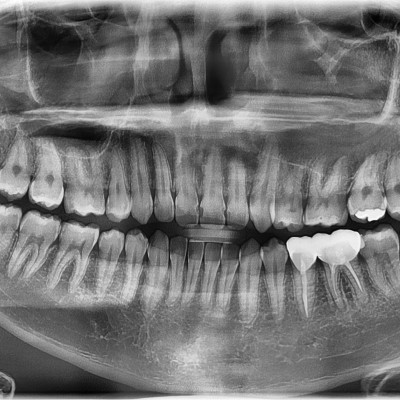

#18,28,38,48 사랑니 발치 #18,28,38,48 사랑니 발치 구강외과 전문의가 당일 발치했습니다.